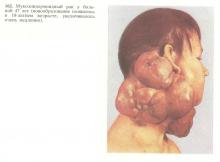

Rosszindulatú daganatos formák mukoepidermoidnoy fordulnak elő a fájdalomtól. Ezek a daganatok vannak rögzítve, ezek beszivárog a bőr, általában sűrű, fájdalmas tapintatú. Néha vannak sipoly levehető emlékeztető sűrű genny. Ilyen esetekben, a tumorok általában csíráznak az állkapocsban (ábra. 162).

Alatt mukoepidermoidnyh daganatok mértékétől függ a sejt differenciálódás: egy kicsit, közepesen vagy jól differenciált típusok. További közös az elmúlt két típusú tumorok (72, 82), ezek zajlik hosszú idő, de ezek a betegek áttétek és a halál. Bármilyen típusú szerkezet mukoepidermoidnoy tumor, amelyet, mint például fájdalom, hiánya elmozdíthatóság, bőr beszűrődése. Malignus természetesen megfigyelhető azon páciensek egyharmadában, metasztázis a regionális nyirokcsomók (szintén megtalálható minden típus) - 25%. Gyengén differenciált radioszenzitívek, szinte minden esetben megtalálható mikroszkópos jele a fellépés a sugárterápia. Más típusú mukoepidermoidnyh sugárzásra daganatok.

A mukoepidermoidnye tumor részén már karéjos szerkezet, ezek a fehér-szürke színű, néha szürkés-rózsaszín folt. Határozott ciszták különböző méretű és összeomlása az üreg tele viszkózus anyaggal, vagy (gyakrabban) genny.